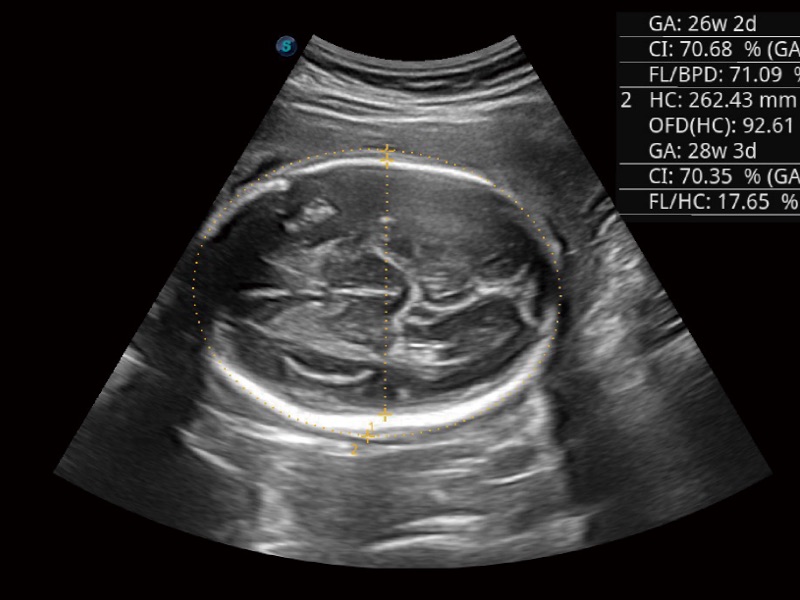

宽频带及多频段变频结合16877太阳集团频率复合技术,使得每一支探头可以很好地给临床带来穿透力与分辨率的完美结合,图像真实,提供临床诊断准确性。

微米成像技术大大提高了器官和病变的可见性。高清对比度分辨率将抑制斑点噪声,同时保持真实的组织结构。

妇产科应用

三维光影成像技术采用新型的渲染方式,增强边缘信息,使得轮显示清晰完整,为临床提供丰富、直观的三维结构,提供临床诊断准确性。